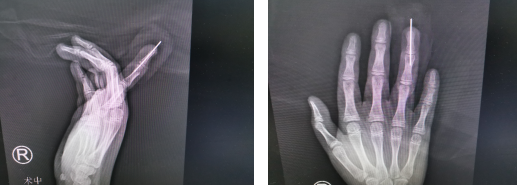

當天,朱主任通過檢查小康的手指和拍攝的X線片立即判斷出,這絕對不是骨折導(dǎo)致的手指畸形,而是一種骨腫瘤!于是朱主任立即安排小康住院并親自為他進行手術(shù)治療,在手術(shù)過程中發(fā)現(xiàn)小康環(huán)指的伸肌腱被腫大的腫物被動牽拉的像紙一樣薄,這就是小康手指不能主動活動的原因。中間頭端有類軟骨樣腫大組織,并且在橈側(cè)的骨皮質(zhì)還有凹形缺損,這些特征符合比較常見的軟骨瘤特征,證實了朱主任的術(shù)前診斷。朱主任將軟骨瘤完整切除并且將伸肌腱緊縮縫合、固定,手術(shù)非常順利。